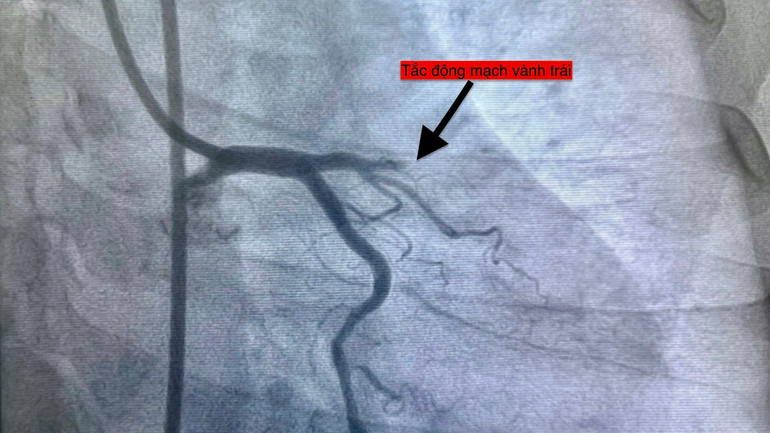

Bệnh viện đa khoa khu vực Thủ Đức vừa ghi nhận liên tiếp bốn ca nhồi máu cơ tim cấp chỉ trong 24 giờ ngày 14/11, một dấu hiệu đặt ra cảnh báo quan trọng về mối liên hệ giữa biến động thời tiết và sức khỏe tim mạch.

Bốn bệnh nhân với độ tuổi từ 51 đến 78, thuộc nhiều nhóm nguy cơ khác nhau đều nhập viện trong tình trạng cấp cứu và được can thiệp mạch vành kịp thời.

Hiện tượng bốn ca liên tiếp trong một ngày là dấu mốc cảnh báo, cho thấy áp lực đang gia tăng lên hệ thống y tế trong bối cảnh thời tiết bất thường. Qua việc can thiệp kịp thời cứu sống các ca bệnh, Bệnh viện đa khoa khu vực Thủ Đức cho thấy năng lực cấp cứu tại đây.